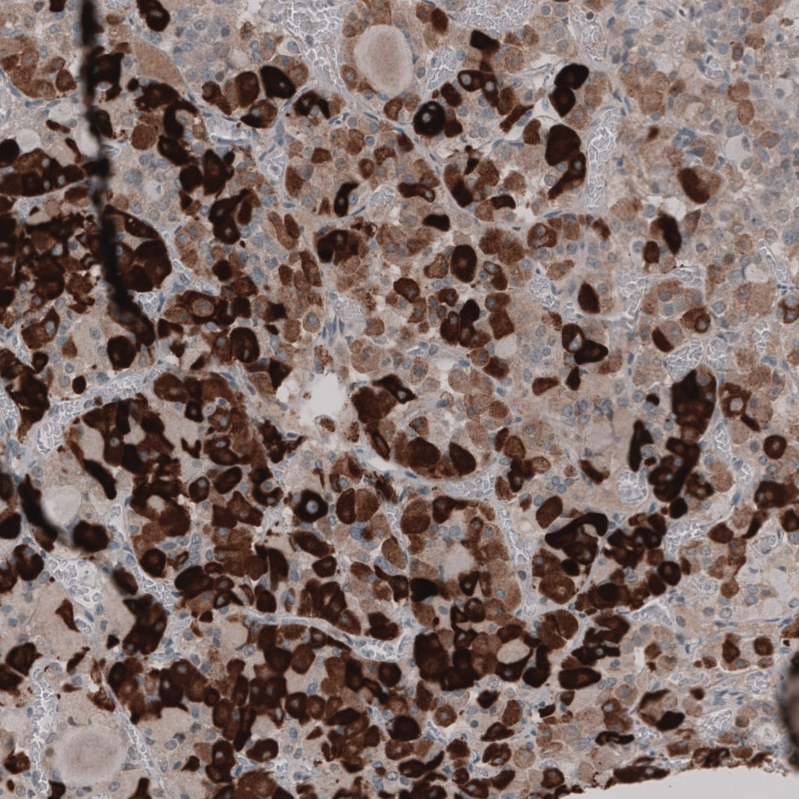

Immunohistochemical staining of human pituitary gland shows strong cytoplasmic positivity in glandular cells.